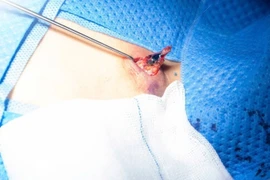

Ê-kíp phẫu thuật bóc đa u xơ tử cung gây dính ruột cho bệnh nhân - Ảnh BVCC

​Trong quá trình phẫu thuật, các bác sĩ ghi nhận nhiều khối u xơ lớn trên bề mặt tử cung. Đặc biệt, bệnh nhân còn mắc lạc nội mạc tử cung tại buồng trứng hai bên, gây dính ruột nhiều vào mặt sau tử cung, làm tăng mức độ phức tạp của ca mổ.

Ê-kíp phẫu thuật đã tiến hành xử trí cẩn trọng các tổn thương dính ruột trước khi bóc tách các khối u xơ bằng phương pháp nội soi.